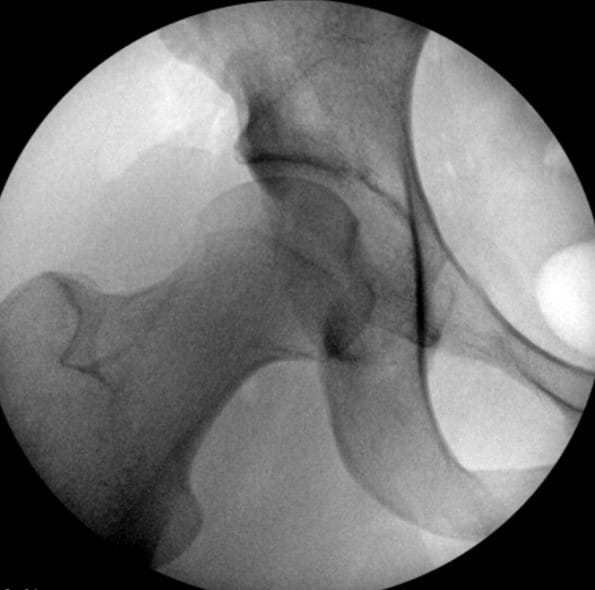

Dr. Salata performs the first stage of the surgery, using arthroscopic techniques to round the femoral head, improve offset and repair labral damage resulting from FAI. The Director of the Joint Preservation and Cartilage Restoration Center and Division Chief of Sports Medicine at University Hospitals Cleveland Medical Center, he is also a Professor at the School of Medicine and Associate Orthopedic Team Physician for the Cleveland Browns.

Without disrupting the sterile surgical field, Dr. Wetzel next scrubs in and employs an open technique to deepen and reorient the hip socket. “Where University Hospitals differs from other places around the country is that we have been able to maintain a partnership that requires two very vastly different skill sets to execute this surgery to the highest level of efficiency and skill,” he says. “We have the ability to rely on each other as knowledge sources and eliminate single-surgeon bias when we discuss treatment plans with patients.”